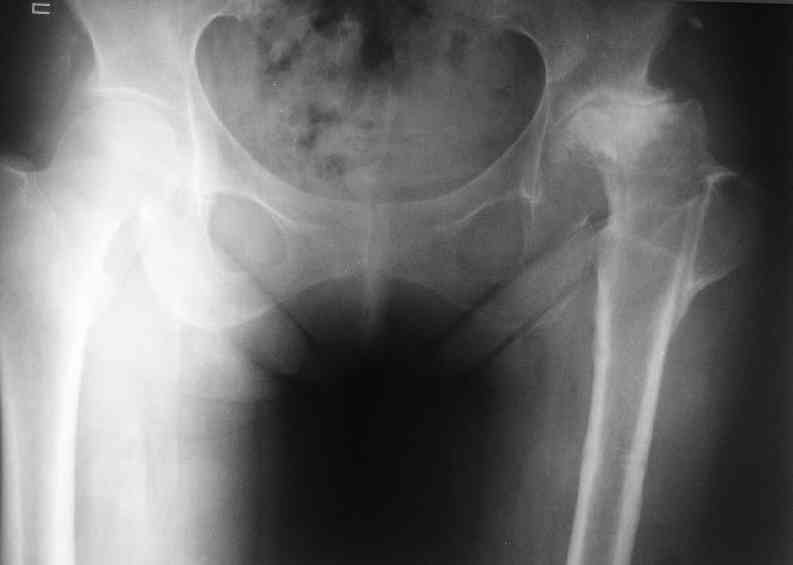

Еще пара фото, ситуация несколько иная, задачи те же, открытое вправление застарелого вывиха в 2002, молодой возраст. Сейчас госпитализирована для эндопротезирования.

А за счет чего такое укорочение? По снимку не видно соответствующего дефекта. Ну плюс приводящая контрактура - но все равно как-то уж больно много. Может, сделать снимки и таза обзорный с обоими проксимальными отделами бедра, и коенный суставов с приложенной линейкой какой?

Судя по снимку, максимум истинное укорочение около 4 см, что может быть коррегировано интраоперационно. Вопрос в другом: куда ставить ацетабулярный компонент в истинную или во вновь сформированную ( впадина диспластичная).

По рентгенограммам укорочение не более 4 см, остальное возможно за счет контрактуры. Опыта с низведением аппаратом Илизарова нет, но мы одномоментно такие укорочения корригировали вполне успешно (в год 5-10 именно таких и проходит). Лишние этапы пожалуй только будут способствовать инфекции. Доступ чаше применяем передне-наружный, а вот протез наверное поставили бы здесь на цементе - остеопороз выражен.

The X ray that you provided does not show 8 cm of shortening. Perhaps you could send one showing the whole pelvis and proximal femurs.

I agree with Dr Eid's comments. The origin of the 8 cm leg length difference is a puzzle. Is this a clinical measurement? In that case contracture of the joint might affect the measurement. Can we see an AP pelvis to include both hip joints (including a calibration object with a known length) so that the difference in leg lengths that can be ascribed to the hip deformity and bony reabsorption can be measured. This sort of xray will help with templating for the TJR also. I would be very tempted to do a one stage procedure and accept some shortening. Shoe lifts should take care of a 3-4 cm difference.

До травмы проблем с ногой не было. Укорочения, болей и т.п. не отмечал. Сегодня перемерял укорочение - меньше 7 см намерять не

По уровню малых вертелов (с учетом рентгеновского увеличения) получается 5 см. Клинически ногу низвести путем тракции невозможно. Из движений - сгибание до 40*, остальные движения "символические".

Ортопедическое укорочение пострадавшей ноги может быть и 7, и 10 см. за счет контрактур в тазобедренном суставе, а вот истинное укорочение, судя по представленным рентгенограммам, вряд ли больше 4 см.

Больного прооперировали на прошлой неделе (цементный протез, цемент с гентамицином). Использовали задне-боковой доступ. В области перелома подвижности практически не было, так что тему сообщения уместно заменить на "неправильно сросшаяся шейка". И в головке, и во впадине

были значительные дегенеративные изменения, так что ни биполяр, ни остеосинтез тут неуместны (хотя это предлагали в ortopod'е). После релиза удлинили ногу на 3 см. Дальше удлинять побоялись из-за

натяжения седалищного нерва, хотя в принципе можно было бы еще 15-20 мм нарастить. По послеоперационной рентгенограмме анатомическое укорочение порядка 15 мм. Клинически при ходьбе - 4 см, но это за счет перекоса таза.

The patient underwent cemented THR on last week. Postero-lateral approach was used. There was only minimal motion at the fracture site and we had to cut the femoral head with oscillating saw. The femoral head was deformed with it's cartilage completely absent in some areas.

Acetabulum showed gross degenerative changes, especially in superior rim. So I think it was right choice not to do ORIF in this case. After some soft tissue release we've lengthened the leg up to 3 cm. Further lengthening was possible but we stopped at that moment due to tension of n. ischiadicus. Now patient walks with crutches. Leg length discrepancy is about 4 cm due to pelvic tilt (discrepancy on post-op x-ray is 15 mm).